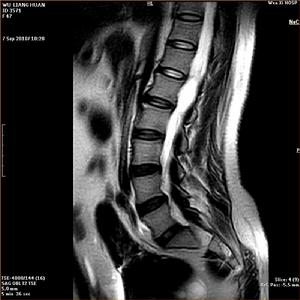

脊髓病變是由於各種原因(如外傷、病毒)等造成的脊髓內部神經

脊髓病變損傷,可能導致患者癱瘓等嚴重後果。